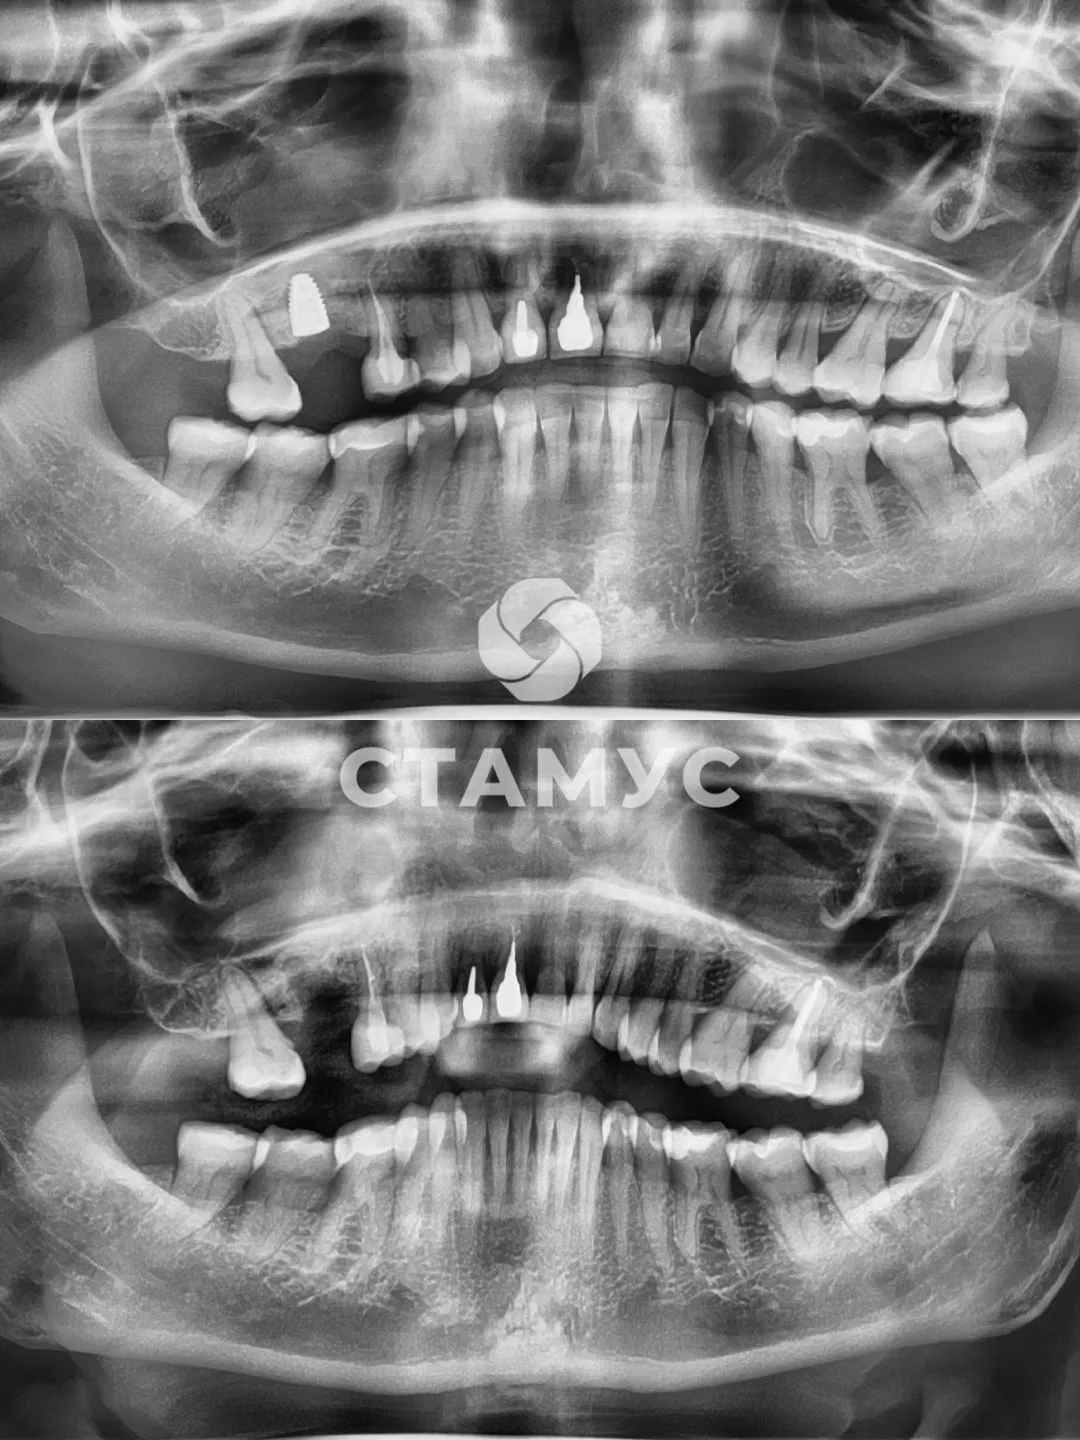

Имплантация зубов

1 зуб

Боль в зубе 1.6 и отечность слизистой

Купирование воспалительного процесса консервативно по поводу обострения хронического периодонтита зуба 1.6 с абсцессом на небе.

Зуб 1.6 удален.

Установлен дентальный имплантат после 2 месячного восстановления.